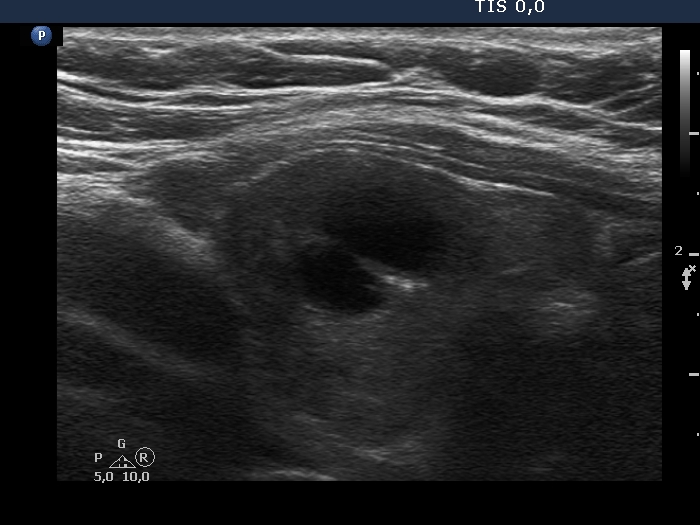

Examination in 2020 (third row of images):

Comment. This story draws attention to how important it may be to be aware of the results of a previous study. By result I do not mean the findings, but the archived recordings.Clinical data: The patient came to a routine follow-up. She had no complaints.

Palpation: Both lobes were a bit firm on palpation. There was a not firm nodule in the right lobe.

Laboratory test: TSH 3.38 mIU/L on daily 125 microgram levothyroxine.

Ultrasonography. The previously cystic lesion has spontaneously decreased in size, the cystic fluid has disappeared. However, the hyperechogenic foci were still visible. If we had only seen this current study, we would have had to regard these echogenic granules microcalcifications.

We recommended that she takes the replacement therapy at the same dose and has a TSH scan after a year and an ultrasound scan after three years.